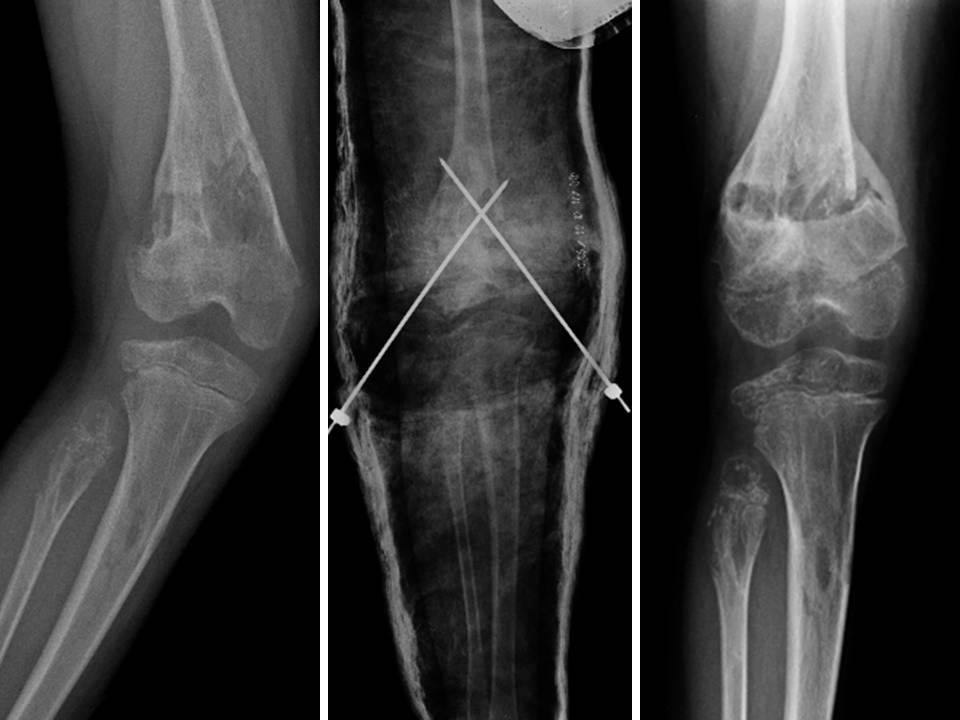

Figg. 11 A-B-C: intervento di osteotomia